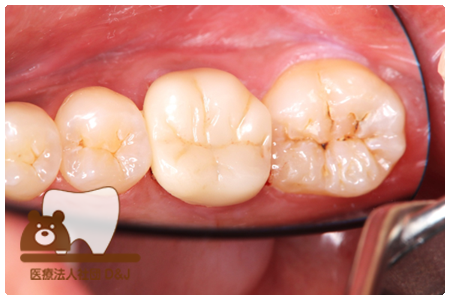

症例3フリジルコニアクラウン 左上6

治療前

治療後

59歳 男性

- 治療内容

- 虫歯で大きく失われた歯に対して、土台としてファイバーコアを使用し、その上にフルジルコニア製の被せ物を装着しました。見た目と強度を両立した自由診療の治療です。

- 治療期間

- 根の治療含めて3カ月半

- 費用

- 自費

フリジルコニアクラウン:77,000円(税込)

(R8.2月時点)

- その他の治療の費用は含まれておりません。

- リスク・副作用

- 強い力が加わると割れる可能性があります。また、噛み合わせや歯ぎしりの影響で脱離することがあります。